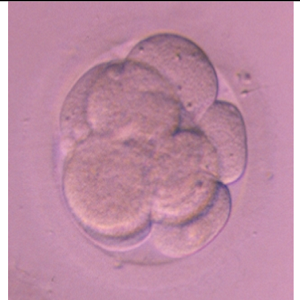

Human day 3 embryo generated in PFM-11 SYNTHETIC PROTEIN-FREE MEDIUM from fertilization up to day 3. The ART-7b and PFM-11 media have been phased out. The SYNBIOS®embyro culture and handling media is an improved formulation over its predecessors, the ART-7b and PFM-11 synthetic protein-free media.